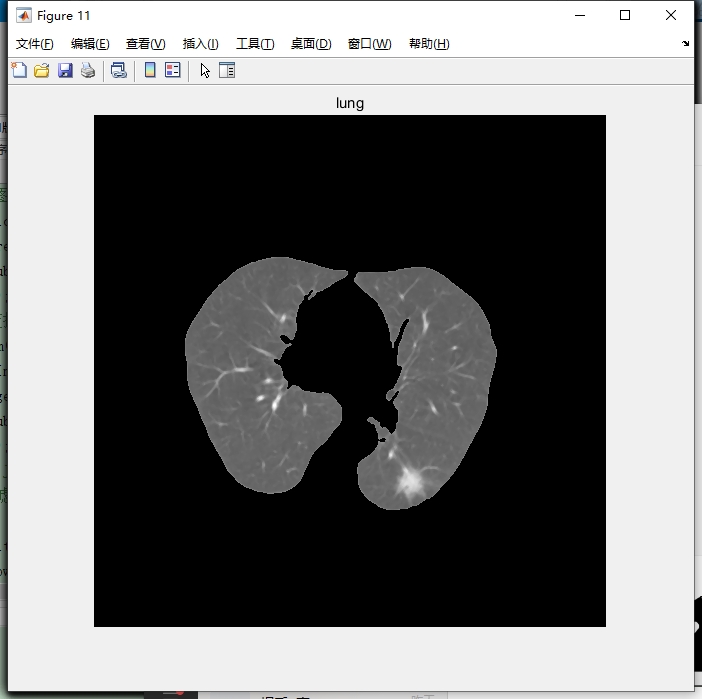

3. 肺质分割

基于阈值分割来从原CT图像中分割出肺质。

% 手动设置一个合适的阈值,这里只是示例,实际可能需调整

threshold = 100;

bw = img > threshold;

代码分析:先设定一个阈值 threshold,这里设为100,但实际应用中要根据图像特点调整。然后通过比较运算 img > threshold,将大于阈值的像素设为1(白色),小于等于的设为0(黑色),得到二值图像 bw,完成初步的肺质分割。